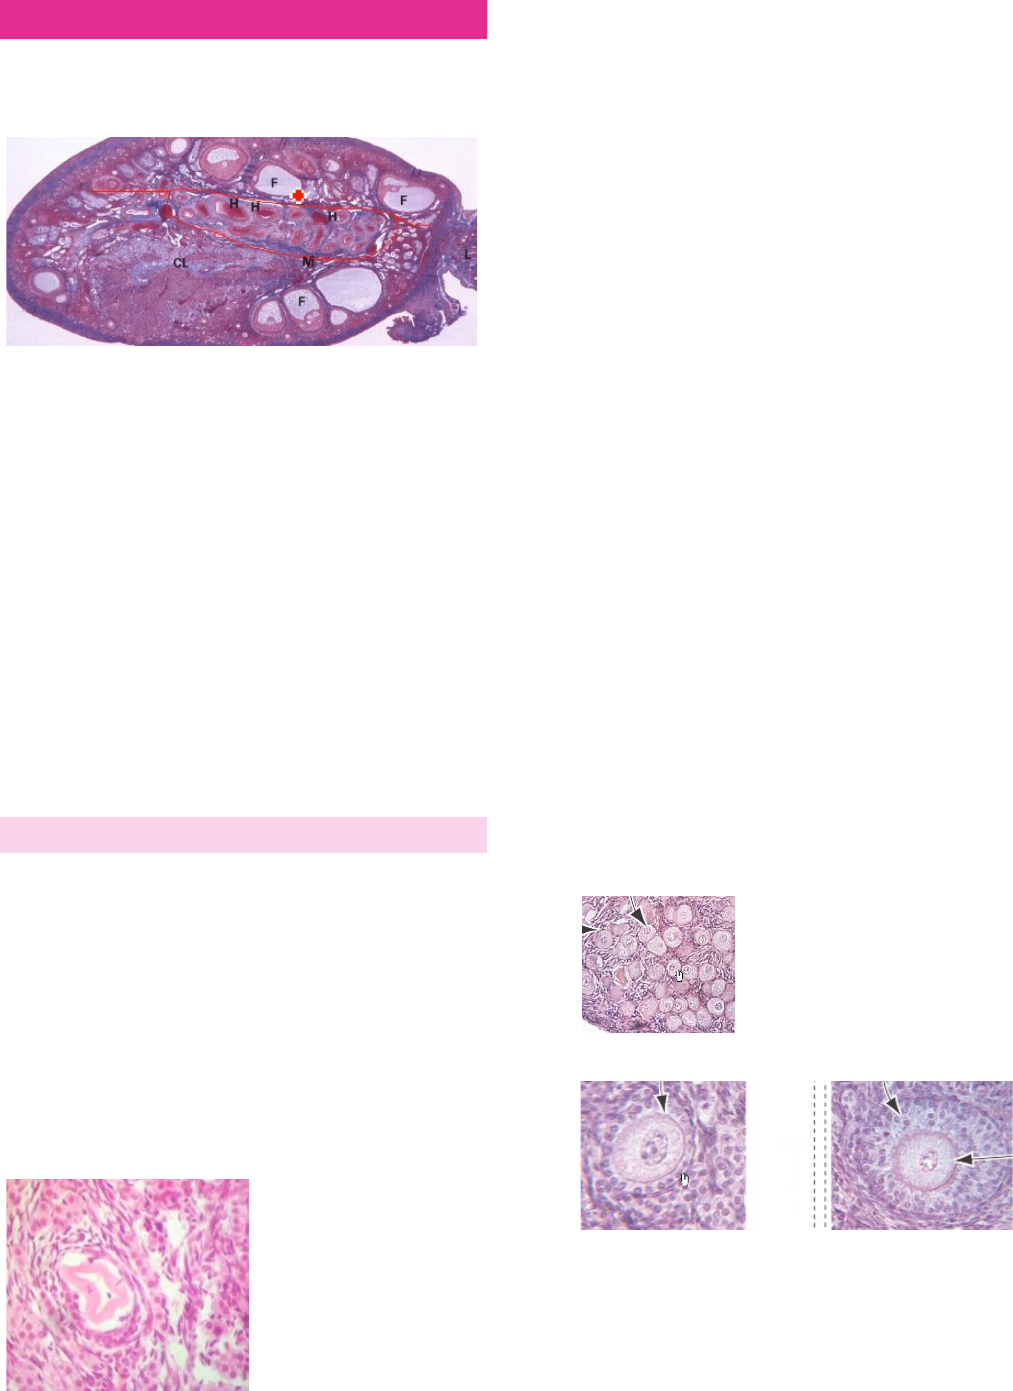

Órgão par, sendo ele a gônada do órgão reprodutor feminino. Faz a produção de hormônios (estrogênio e progesterona) e de gametas (ovócito secundário).

Região medular: possui vasos sanguíneos e tecido conjuntivo. É a região onde os vasos entram e saem do ovário (hilo ovariano), e está marcado com um círculo vermelho.

Região cortical: é a única região onde estão os folículos ovarianos (letra F na imagem), e ao redor deles, estão o estroma, que é formado por um tecido conjuntivo frouxo.

Túnica albugínea: camada fibrosa que reveste o ovário.

Obs.: antes da puberdade, temos somente folículos primordiais (menores e estão perto da túnica albugínea). Após a puberdade, esses folículos primordiais entram em processo de amadurecimento.